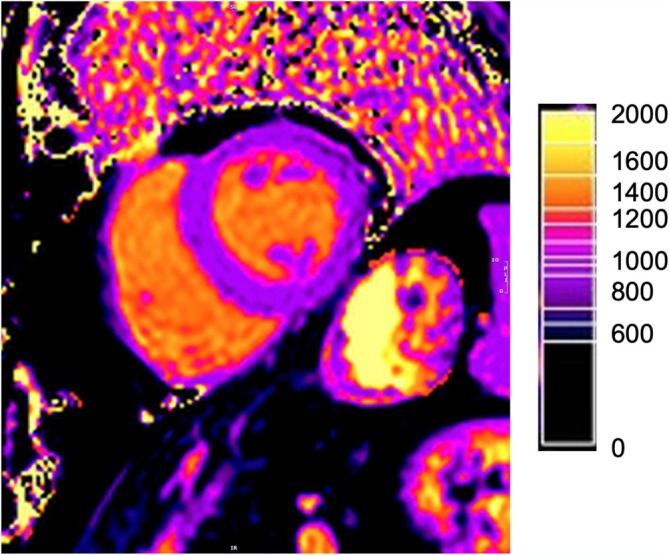

Abstract Image